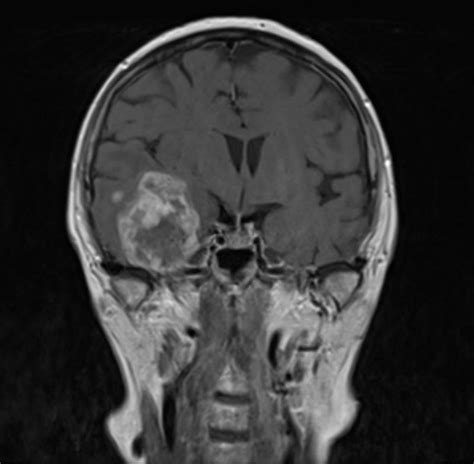

Imagistica prin rezonanță magnetică (IRM) cu substanță de contrast pe bază de gadoliniu (SCG) este metoda de elecție utilizată în stadializarea și monitorizarea cancerului rectal. Cu toate că SCG prezintă un profil ridicat de siguranță, au fost raportate cazuri de reacții de hipersensibilitate (RH), chiar cu mecanism imunologic (mediat de IgE sau prin limfocite T) dovedit prin testare cutanată. Un pacient în vârstă de 54 de ani, diagnosticat cu adenocarcinom rectal chimiotratat neoadjuvant, a fost evaluat pentru un episod de erupție urticariană generalizată, asociată cu angioedem facial și labial, apărute la cinci minute după administrarea de acid gadoteric în timpul unei investigații IRM.

Pacientul nu a mai fost expus anterior la SCG. Testarea cutanată intradermică la SCG inductor și la o alternativă (gadobutrol) cu concentrația maximă noniritativă a fost pozitivă la citirea imediată, certificând un mecanism IgE-mediat. Administrarea tot mai frecventă a SCG și necesitatea utilizării acestora în monitorizarea unor afecțiuni impun evaluarea alergologică riguroasă în cazul apariției RH. Cazul pacientului nostru reprezintă o RH manifestată la primul contact cu substanța de contrast paramagnetică, cu teste cutanate pozitive. Nu sunt complet înțelese mecanismele prin care reacțiile de hipersensibilitate la SCG pot apărea fără o expunere anterioară la acestea.